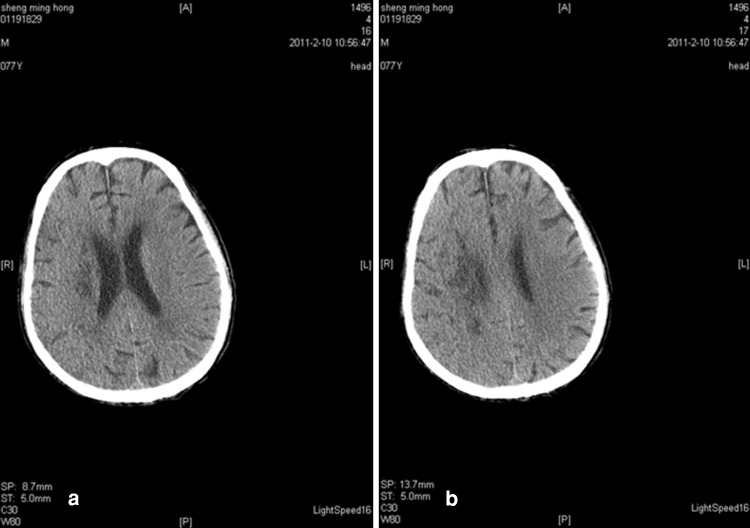

Upon hospital admission, urine flow cytometric analysis was normal, and renal function tests indicated third stage CKD (Table 2). During hospitalization, blood analysis showed that white blood cells were 8.20 g/l (the reference range was 4–10 g/l) and neutrophils were 91.90 % (the reference range was 50–70 %). Chest X-rays indicated infection in the lower sections of both lungs. A color Doppler ultrasound probe of the urinary system showed that the kidneys were normal with smooth encapsulated membranes. The left kidney section was 102 × 51 × 45 mm, and the right kidney was 94 × 49 × 44 mm. In addition, the renal-to-renal sinus proportion was normal; there was no separation between the renal pelvis and calyces, no expansion of the ureter, and no abnormal echo in the bladder area. Blood flow was significantly elevated in the initial renal artery segments, and the resistance index was high, which suggested that the initial renal artery segments were mildly stenotic (Table 3) [4]. Three days after the cerebral infarction, urine flow cytometry was normal. Blood gas analysis showed a pH of 7.531 (the reference range was 7.35–7.45), a carbon dioxide partial pressure of 28.10 mmHg (the reference range was 35.25–45 mmHg), and an oxygen partial pressure of 80.40 mmHg (the reference range was 94.50–99.76 mmHg). In addition, the actual bicarbonate, standard bicarbonate, whole blood buffer base, base excess, and oxygen saturation were all within their normal ranges. As of 16 February 2011, ten blood electrolyte tests showed that potassium, sodium, chloride, and calcium were within their normal ranges. At 22 h after the onset of the sickness, a brain CT scan indicated low-density spots in the right parietal occipital area and corona radiata region. In addition, the sulcus and grooves were wider and deeper, but there was not a shift in the midline structures. Thus, we concluded that the right parietal occipital area and corona radiata had suffered from brain infarction and brain atrophy (Fig. 1). Five days after the onset of the sickness, another brain CT scan indicated low-density spots and flakes in the right parietal occipital area and corona radiata. Compared with the previous scan, there were new lesions, and the sulcus and grooves were wider and deeper, but there was still no shift of the midline structures, which led us to the same conclusion as the previous findings (Fig. 2).

Fig. 2.

a, b CT scan of the brain 5 days after the onset of the stroke. Low-density spots were seen in the right parietal occipital lobe and corona radiata. The right parietal occipital area and corona radiata showed flaky low-density spots. A comparison of the two CT scans shows that new lesions were detected at 5 days